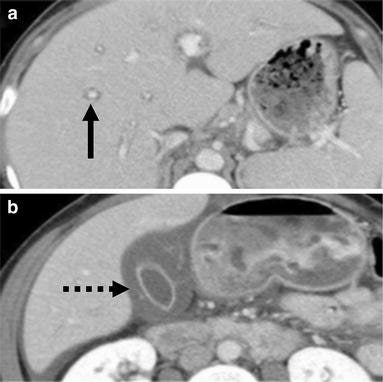

간 석회화와 간경화의 차이점은 무엇입니까? 간경변증은 간세포 섬유조직의 대량 증식, 간 내 소담관의 압박, 다수의 소엽 형성으로 간 전체의 간경변증을 일으키는 것으로 알려져 있다. 실제로 간문맥고혈압, 비장종대 등의 간석회화는 대부분 간에서 석회화점을 형성하는 작은 돌에 의해 발생하며, 담즙정체, 배설불량, 담관벽에 담즙색소 침착 등으로 인해 결석으로 이어지는 경우가 많다. . 작은 석회화된 병변. 간경변증의 예후는 문맥압항진증, 복수, 비장종대를 초래합니다. 그 중 간염 간경화 환자는 점차 원발성 간암으로 발전하여 환자의 건강을 심각하게 위협합니다. 간 석회화는 일반적으로 간의 작은 병변이며 일반적으로 간 기능을 손상시키지 않으며 주기적으로 검토할 수 있습니다. 간 석회화는 비교적 크며 간의 특정 부위에 국한되어 복통, 발열, 간기능 저하 등을 동반하므로 수술적 치료를 고려할 수 있다. 수술 후 절제술은 일반적으로 좋습니다. 간경변증과 간석회화는 병인, 질환의 변화, 인체에 미치는 영향, 예후 등에서 차이가 있음을 알 수 있으며, 간석회화의 예후와 임상적 특징은 간경변증에 비해 양호하다.